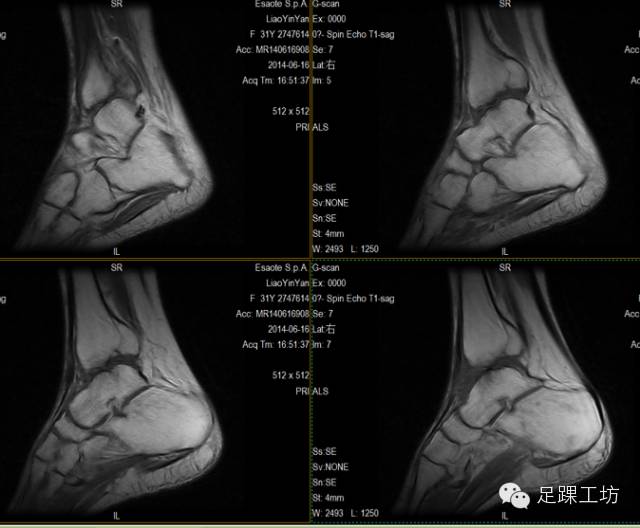

MRI